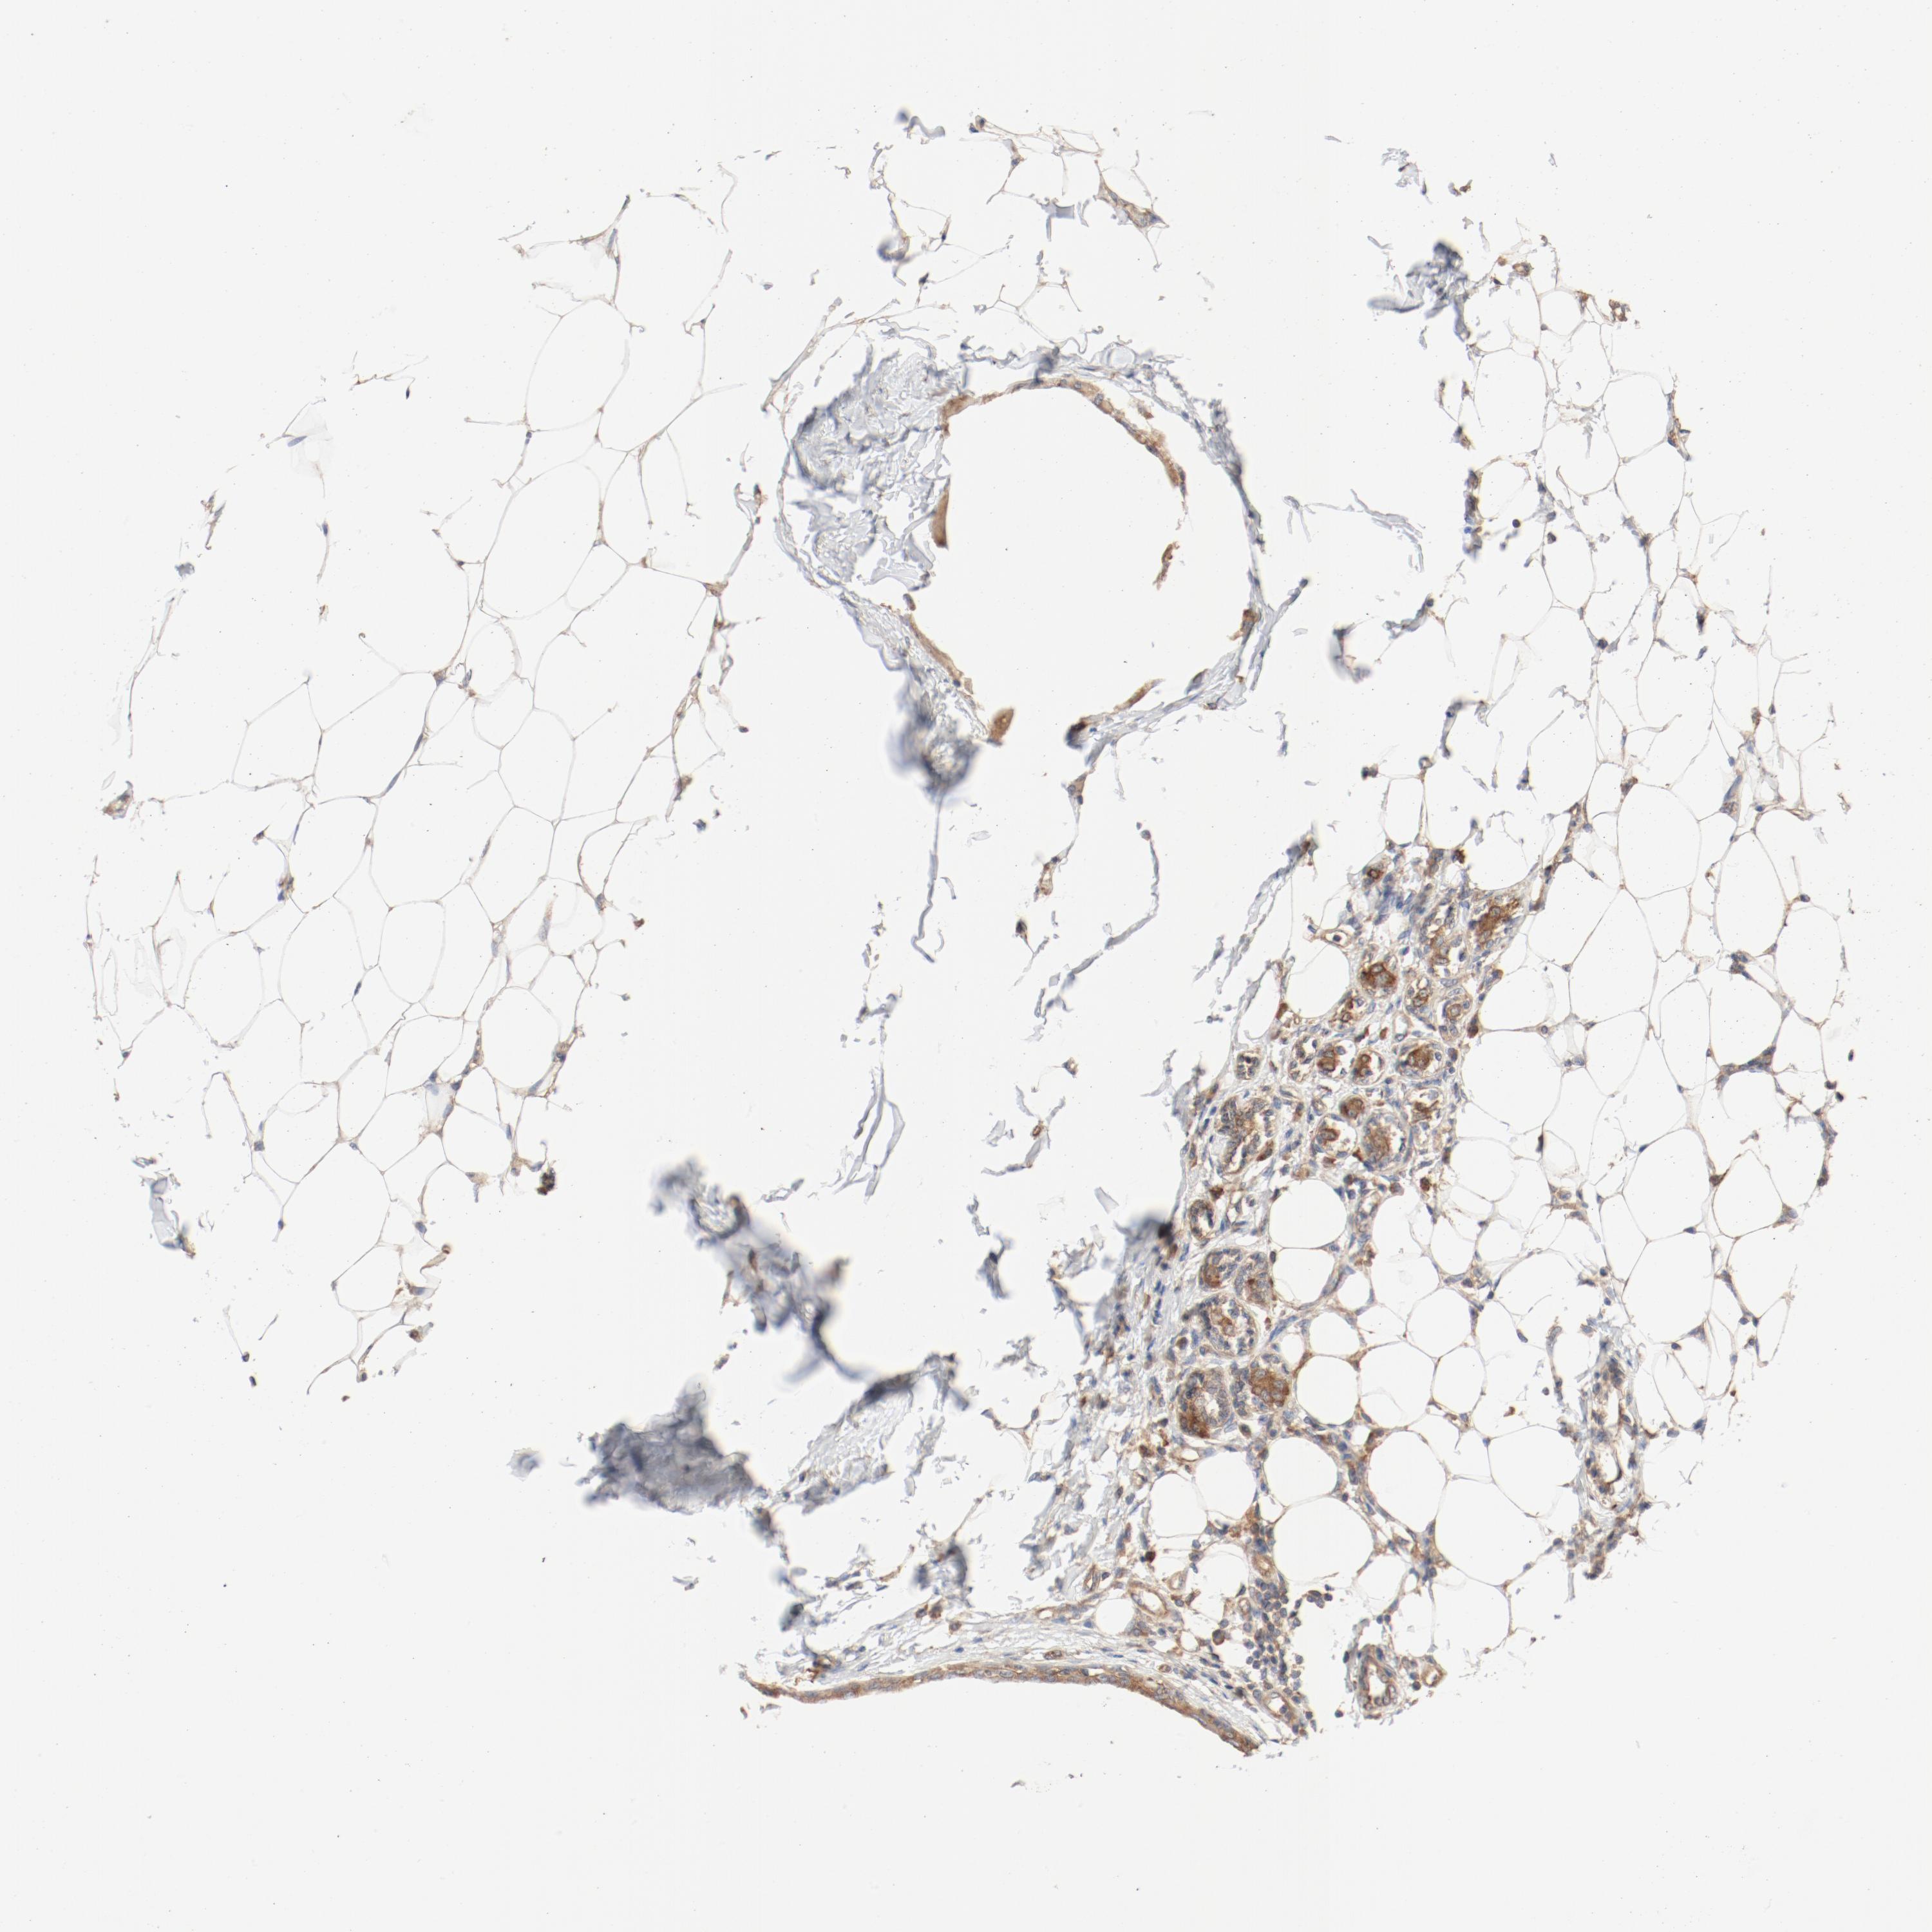

CANCER BREAST CANCER Show tissue menu

BRCA TCGA BRCA VALIDATION PROTEIN EXPRESSION

ANTIBODIES

AND

VALIDATION